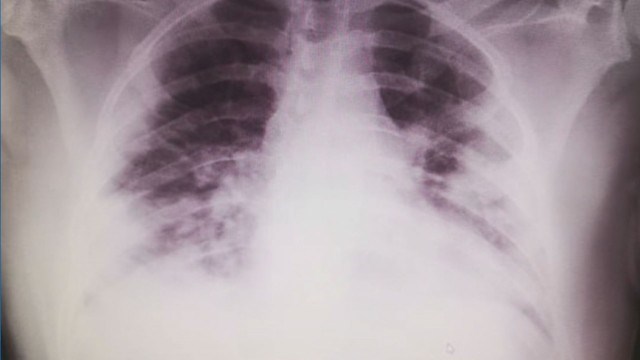

Медикът показа рентгенова снимка на белите дробове на пациента, на която се вижда, че има частична загуба на тъкан в органа, която води до дихателна недостатъчност. Лекарят апелира да не се вярва на конспиративните теории, защото те могат да бъдат опасни.